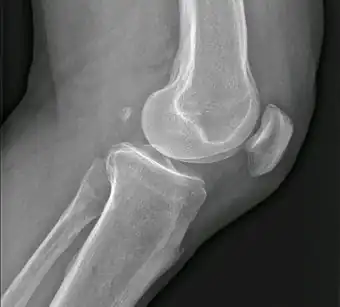

![]() Fabela es la pequeña osificación en situación posterior de los cóndilo femorales. | ||

El fabela, también conocido como fabella (del diminutivo latino de faba, 'haba'), es un pequeño hueso sesamoideo que se encuentra en algunos mamíferos incrustado en el tendón de la cabeza lateral del músculo gastrocnemio (gemelos) detrás del cóndilo lateral del fémur.

Es una variante de la anatomía normal, presente en los seres humanos entre el 10 y el 30 % de los individuos. En raras ocasiones, hay dos o tres de estos huesos (fabela bi- o tripartita). Puede ser confundido con un cuerpo suelto o de osteofitos.